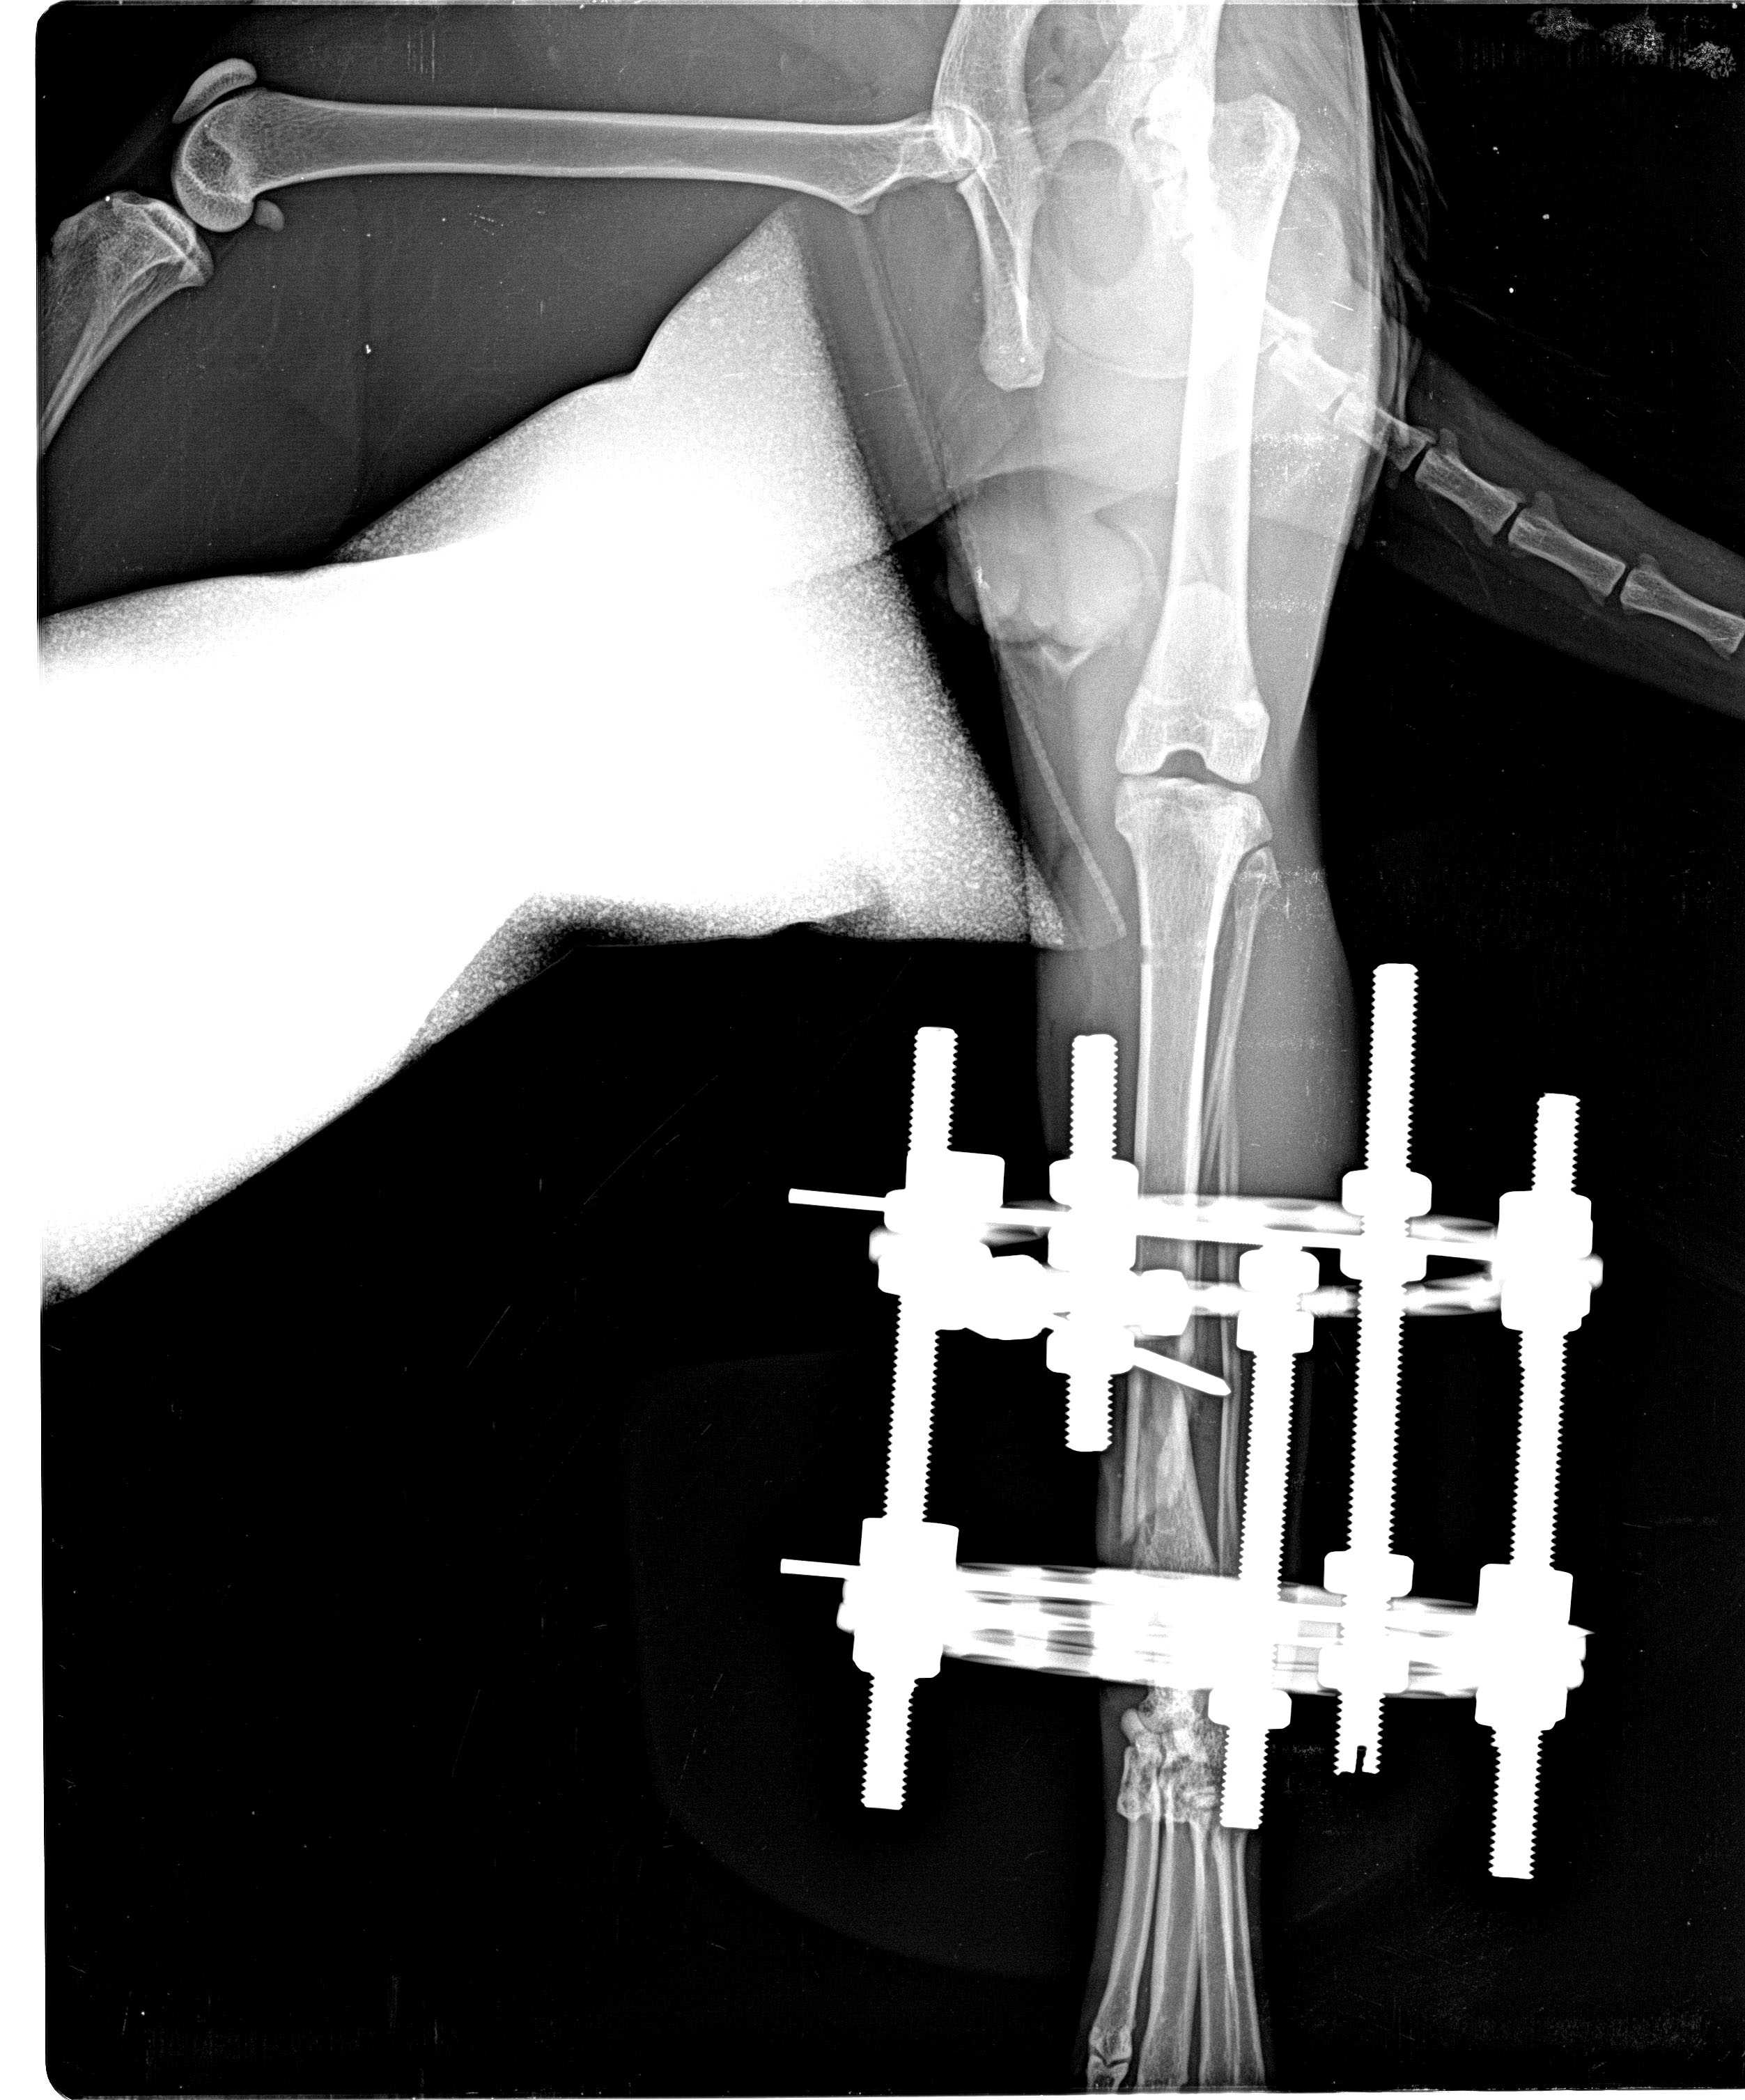

Το εκτόπισμα του Αλέκου, όπως αποδείχτηκε, ήρθε σε σύγκρουση με την κυριαρχική, έως και δεσποτική, προσωπικότητα κάποιου από τη γειτονιά. Και καθώς ο Αλέκος δεν υπολόγιζε την ανθρώπινη δύναμη του κακού, δέχτηκε τις συντριπτικές της συνέπειες στο ποδάρι του... Και μιλάμε για το πίσω πόδι του. Την έφαγε, προφανώς, μπαμπέσικα από χέρι δυνατό και οργισμένο. Συντριπτικό κάταγμα κνήμης και περόνης.

Η Έμιλυ (η κτηνίατρος που τον έβλεπε), μας είπε ότι τα πράγματα είναι πολύ σκούρα για τον Αλέκο. Μας είπε, όμως, ότι στη Λευκάδα ένας συνεργάτης της, Αλέκος κι αυτός, κτηνίατρος, είναι στα ορθοπεδικά κορυφαίος.

Ο Αλέκος μας, έτσι, πέρασε στα χέρια του Αλέκου Υφαντή. Έγινε στο ποδαράκι του Αλέκου εφαρμογή εξωτερικής συσκευής-μινιατούρας Ilizarov. Τα θραύσματα οστών αφαιρέθηκαν και εισήχθη κάποιο πρωτοποριακό υλικό για οστεογένεση. Τέσσερις ώρες χειρουργείο, με τον Υφαντή να εξέρχεται κάθιδρος κρατώντας στην αγκαλιά του τον ναρκωμένο ακόμα από την αναισθησία Αλέκο. Αλέκος και Αλέκος πέτυχαν το ακατόρθωτο! Ο μεν πρώτος κατάφερε και έδεσε με τα στεφάνια και τις βελόνες του Ilizarov, στη μικροκλίμακα της γάτας, ένα πόδι που, υπό άλλες συνθήκες, θα είχε ακρωτηριαστεί. Ο δε δεύτερος υπέμεινε, Γενάρη μήνα(!), εγκλεισμό σε ένα δωμάτιο και ένα πελώριο για τα δεδομένα του μηχανισμό -σχεδόν μισού κιλού- να είναι καρφωμένος στο πόδι του. Η αποθεραπεία με το μηχανισμό πήρε δυόμιση μήνες, πολύ γρήγορη για τη βαρύτητα του κατάγματος. Το πόδι του Αλέκου αποκαταστάθηκε σχεδόν πλήρως. Ο Αλέκος βγήκε ξανά περήφανος στη γειτονιά και ο εχθρός του, μετά από δυόμιση μήνες εξαφάνισής του, δεν θα πίστευε στα μάτια του.

Ο Αλέκος μας, έτσι, πέρασε στα χέρια του Αλέκου Υφαντή. Έγινε στο ποδαράκι του Αλέκου εφαρμογή εξωτερικής συσκευής-μινιατούρας Ilizarov. Τα θραύσματα οστών αφαιρέθηκαν και εισήχθη κάποιο πρωτοποριακό υλικό για οστεογένεση. Τέσσερις ώρες χειρουργείο, με τον Υφαντή να εξέρχεται κάθιδρος κρατώντας στην αγκαλιά του τον ναρκωμένο ακόμα από την αναισθησία Αλέκο. Αλέκος και Αλέκος πέτυχαν το ακατόρθωτο! Ο μεν πρώτος κατάφερε και έδεσε με τα στεφάνια και τις βελόνες του Ilizarov, στη μικροκλίμακα της γάτας, ένα πόδι που, υπό άλλες συνθήκες, θα είχε ακρωτηριαστεί. Ο δε δεύτερος υπέμεινε, Γενάρη μήνα(!), εγκλεισμό σε ένα δωμάτιο και ένα πελώριο για τα δεδομένα του μηχανισμό -σχεδόν μισού κιλού- να είναι καρφωμένος στο πόδι του. Η αποθεραπεία με το μηχανισμό πήρε δυόμιση μήνες, πολύ γρήγορη για τη βαρύτητα του κατάγματος. Το πόδι του Αλέκου αποκαταστάθηκε σχεδόν πλήρως. Ο Αλέκος βγήκε ξανά περήφανος στη γειτονιά και ο εχθρός του, μετά από δυόμιση μήνες εξαφάνισής του, δεν θα πίστευε στα μάτια του.